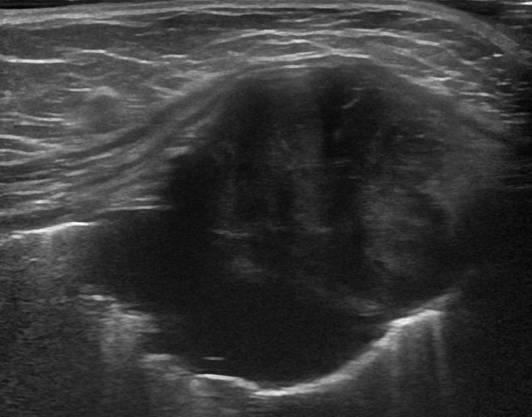

Di căn thành ngực

» Thông tin: Nam giới – 64 tuổi.

» Lâm sàng: Khối thành ngực / K vòm.